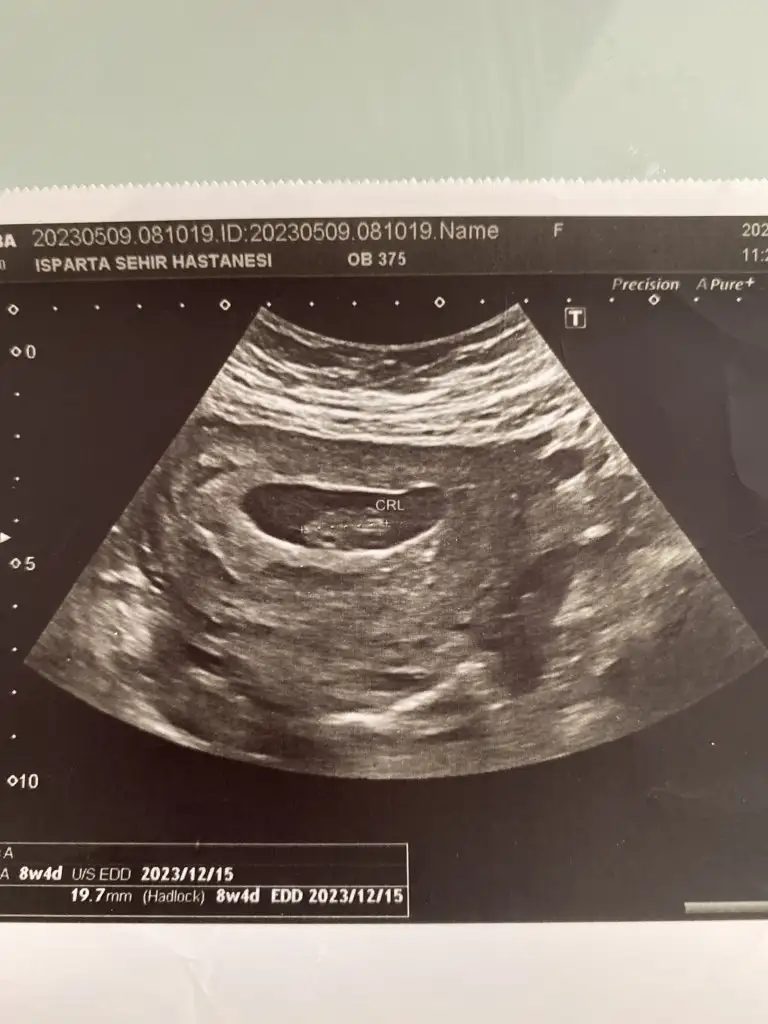

Herkese günaydın. Ben dün ikili test sonucumu almaya gittim, gitmişken de muayene olayım dedim bebek duruyor mu diye

doktor o sırada bir şeyle meşguldu, asistanı baktı, sekreteri de bilgisayardan asistana okudu riskleri. Yaş riski hariç düşük çıktı (yaş 1/59, down 1/1035 trisomi 18 13 1/300000 civarı). Güzel dediler (yaştan dolayı zaten fetal yaptıracağımı biliyorlardı) sonra sonucu istedim ama devlet hastanesi olduğu için yazıcıya gönderiyorlar, çıkarken alıyorsunuz bankodan. Alınca kan değerlerimin birinin yüksek olduğunu fark ettim. Serbest beta hcg 2.33 mom (papp-a mom 1.84) çıkmış ve doktorla konuşma şansım olmadı hiç (muayene sırasında riskler konuşuldu sadece kan değerlerini okumadı sekreter, gündeme gelmedi yani), bugün fetal için kan vereceğim ama geceden beri sözelci-dilci halimle tıp makalelerini tarıyorum (kimi 1.5 mom üstü kimi 2.5mom üstü yüksek kabul ediyor ve down olasılığına ek olarak preeklamsi, hipertansiyon vb gibi birçok gebelik komplikasyonuna işaret edebileceği söyleniyor, çoğu bulgu papp düşük bu yüksekse sorun diyor ama atipik bulgular da büyük bir oranı oluşturuyor vb.) şu aşamada burada böyle bir deneyimi olan yoktur muhtemelen ama yine de belki bir fikri olan vardır diye yazmak istedim. Bir de kombine risk, biyokimyasal risk vb hesaplanmamış hiç. Acaba riskleri hesaplarken kan değerlerini dahil etmediler mi demek oluyordur bu? Fetal için kan vereceğim bugün ama sonucu bekleyebilir miyim bilemedim.